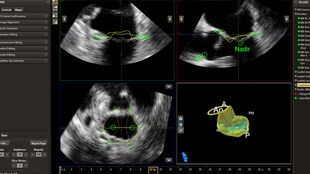

Quali sono le opzioni di trattamento per un paziente affetto da rigurgito mitralico? Se il paziente non è candidato all'intervento a cuore aperto, è possibile considerare la riparazione transcatetere della valvola mitrale (TMVR, Transcatheter Mitral Valve Repair). Oggi, soluzioni di imaging innovative e dispositivi moderni offrono opzioni alternative per alcuni pazienti.